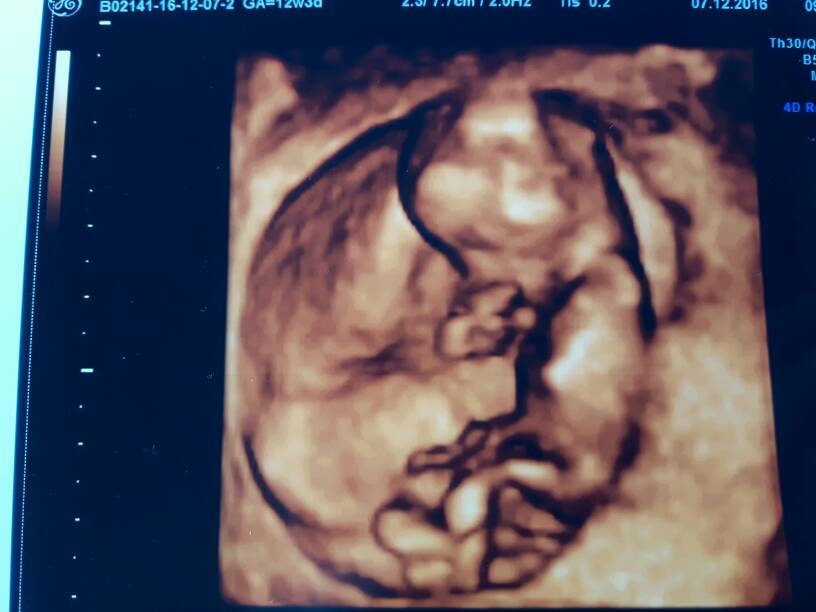

Madzien1234 gratuluję udanej wizyty i pięknych zdjęć synusia [emoji4]